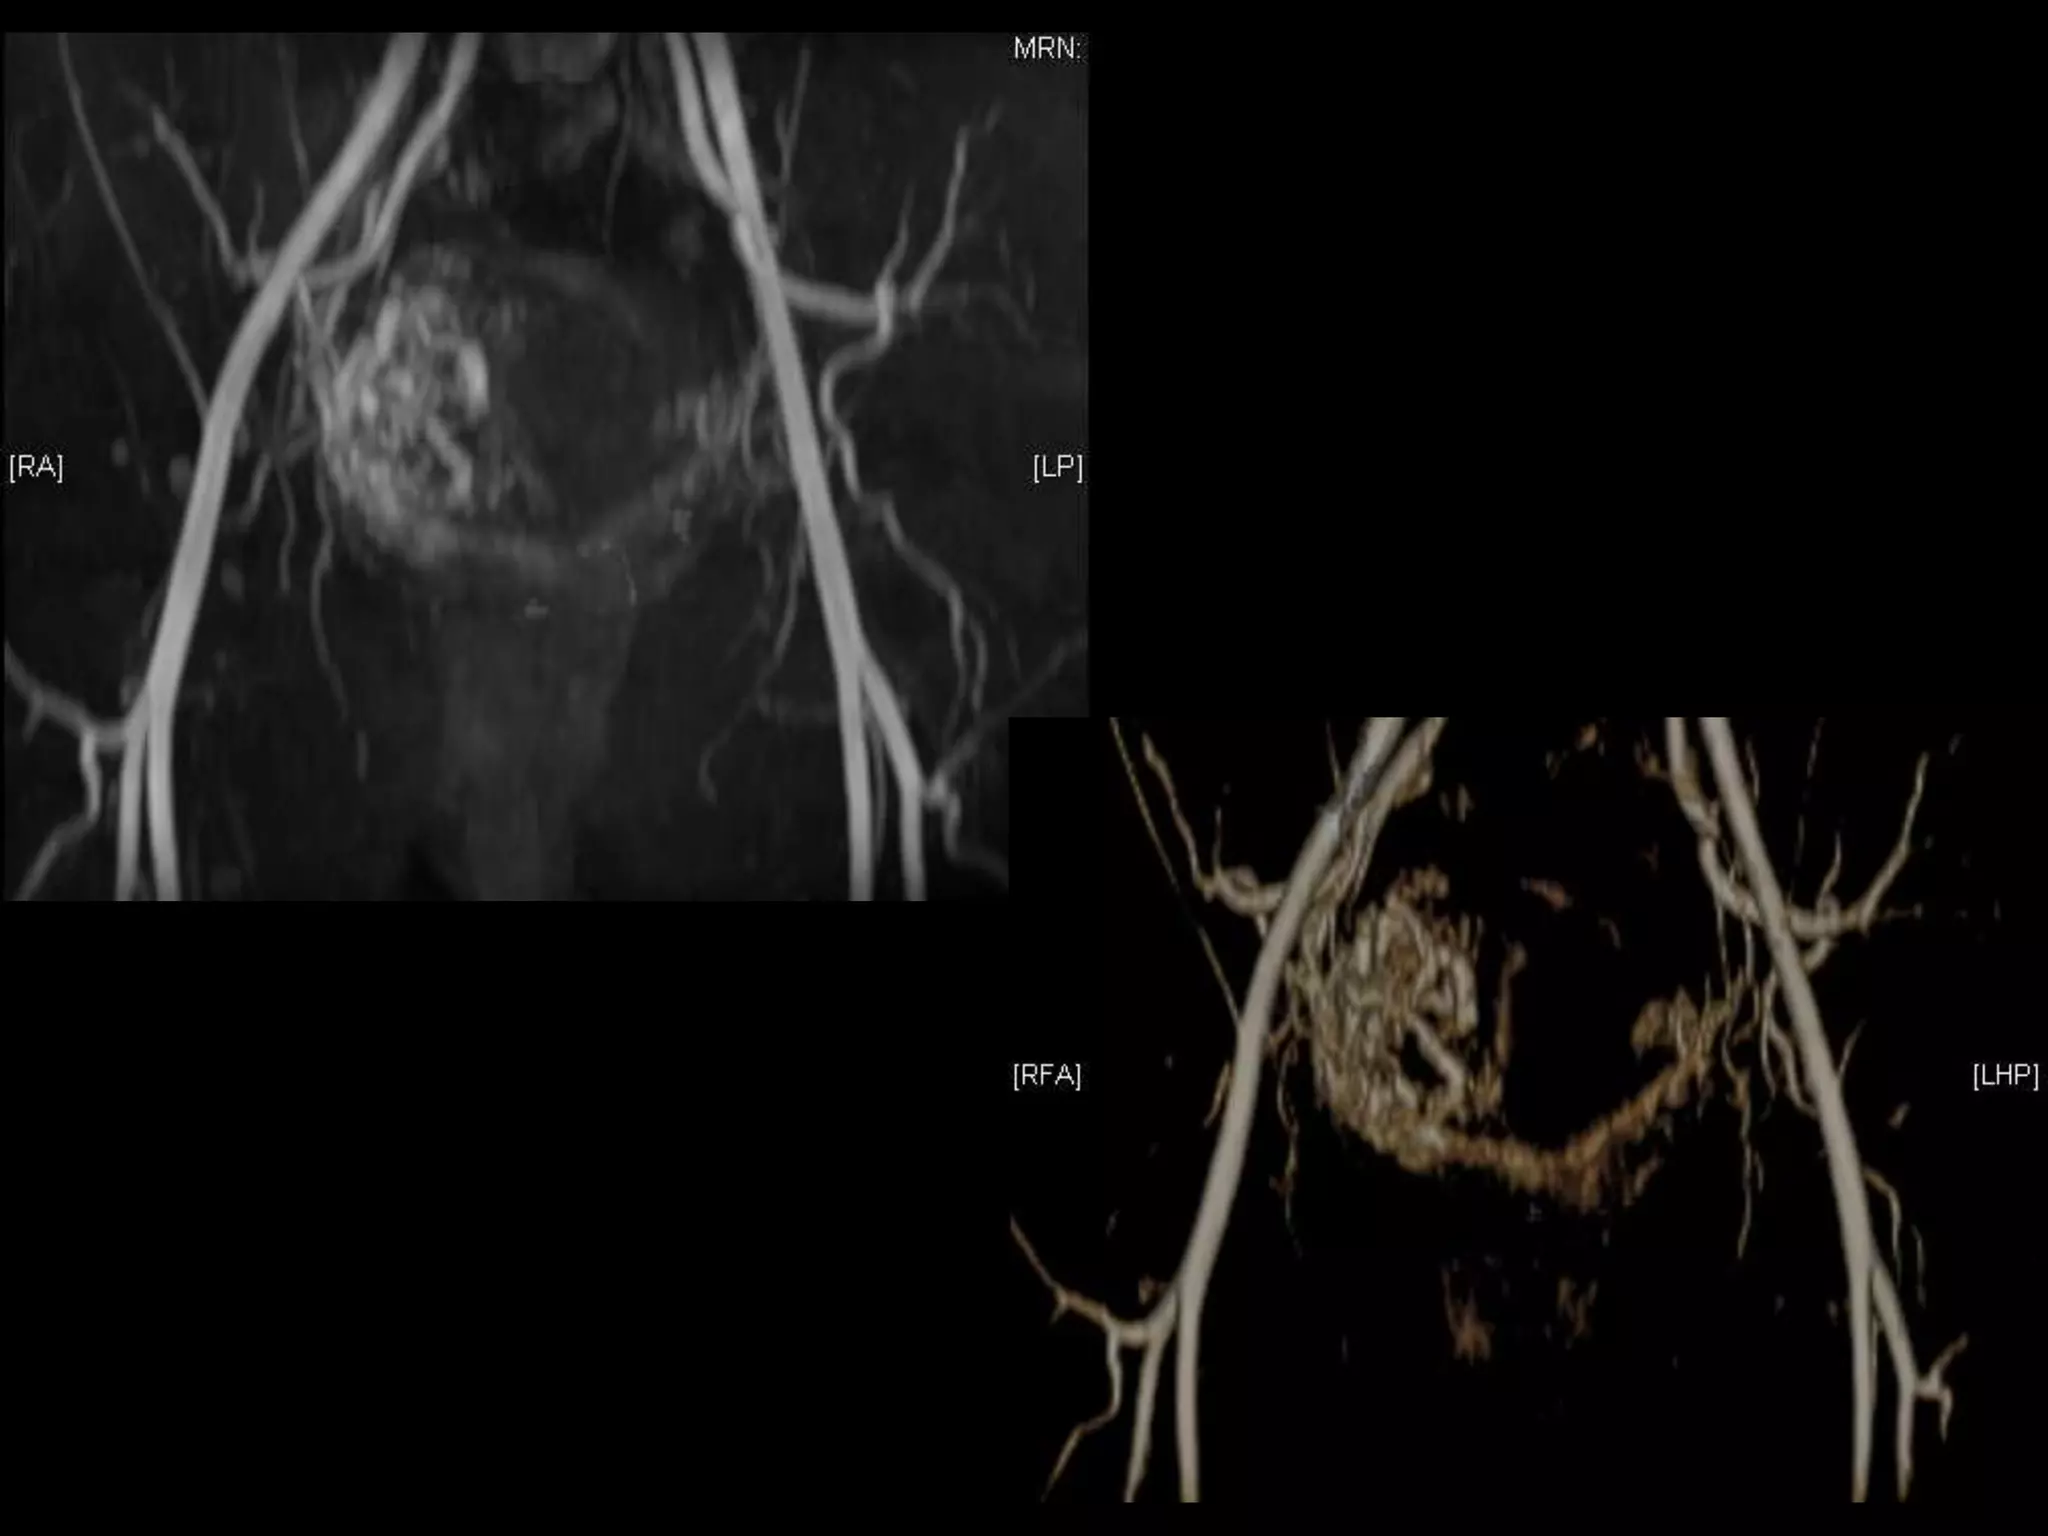

D&C complicated byPerforation, AVM w RPOC at Site of Perforation โ€ข AVM โ€“ Acquired or Congenital โ€ข Acquired โ€“ Traumatic โ€“ D&C, TAB, uterine surgery โ€“ Less common: Endometrial / Cervical CA, GTD โ€“ Clue on US: numerous tortuous vessels, high velocities โ€ข Tx: โ€“ transcatheter arterial embolization โ€ข Potential to preserve fertility โ€“ UA ligation, hysterectomy

POST PROCEDURE S/P embolizationof right UA and left UA due to cross collateralization

1 month followup HCG < 5 mIU/mL No flow in area โ€“ smaller in size Felt residual hematoma Will continue US follow up